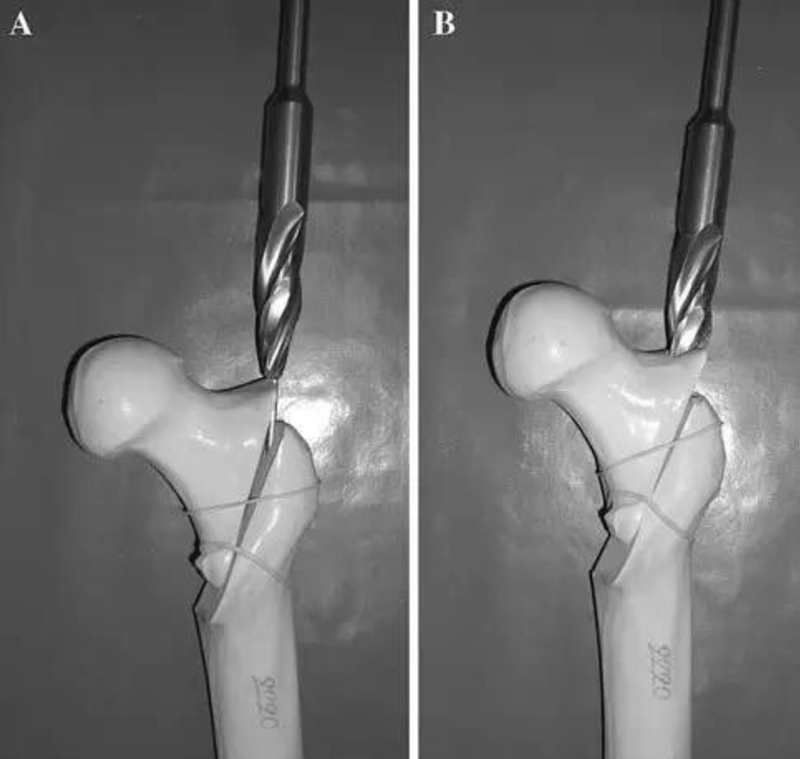

采用过度牵引方法是关键,先不要追求解剖复位。确定导针的位置以后,图A:将扩髓钻顶住近侧骨折块的外缘,开始扩髓;图B:扩髓钻打磨掉近侧骨折块外侧。

图8 A:将扩髓钻顶住近侧骨折块的外缘,开始扩髓;B:扩髓钻打磨掉近侧骨折块外侧。

然后放松牵引,解除过牵,骨折解剖复位以后再向远端扩髓、置钉,即可获得完美的复位固定。